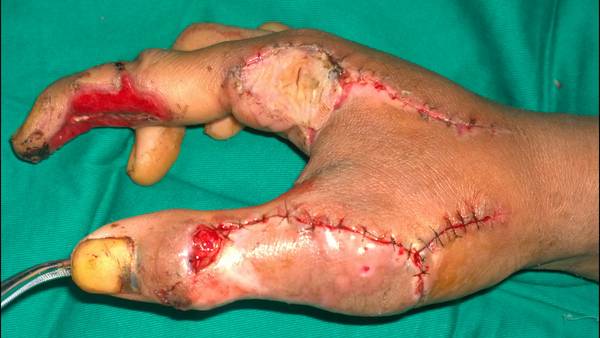

[手指再造] 残指重建拇指

把一个烂手,能保到这种程度,很不错!顶一个

残肢再利用,不错的手术。

今天上传术中及近期术后的图片

请问中指缺损是取腕部游离皮瓣修复的吗?

是的